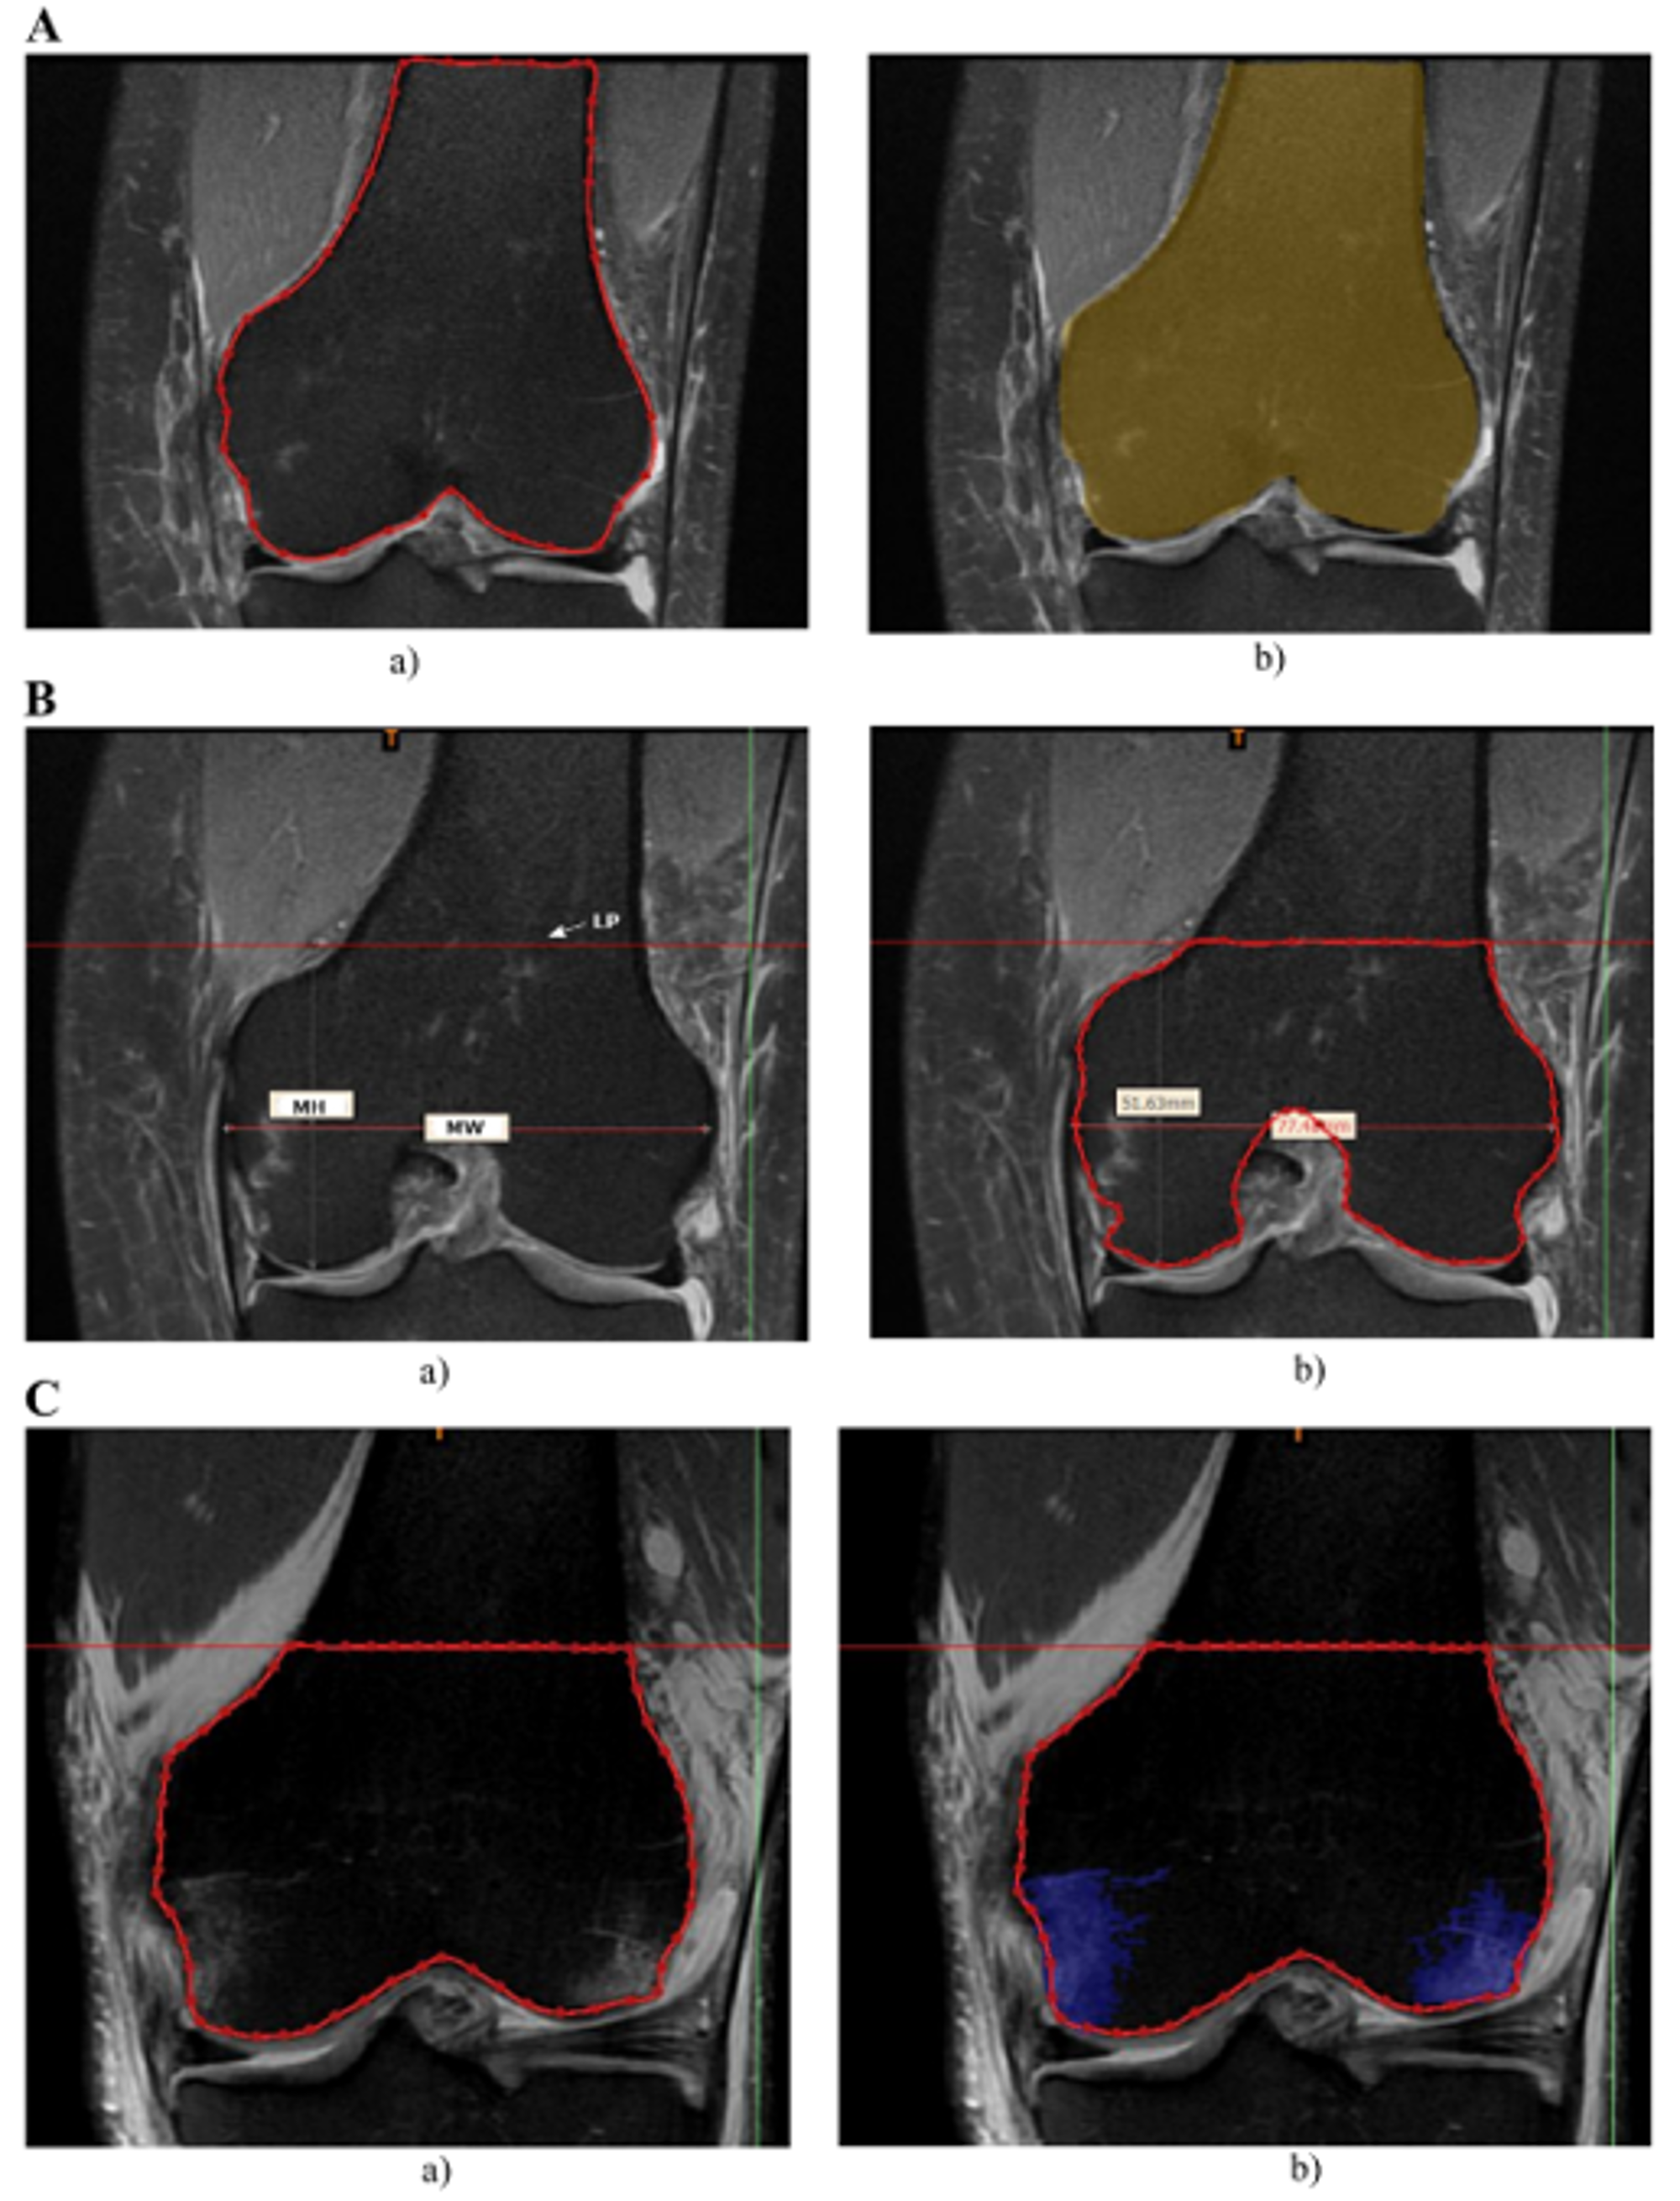

2.1. Measurements of Bone Bruises

2.2. Determining Total Bone Volume

2.3. Segmentation of BB

- in femur:

- in tibia: